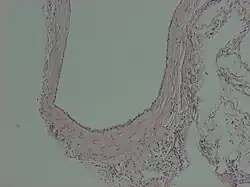

Peritoneal inclusion cyst

A peritoneal inclusion cyst is a cyst-like structure that appears in the pelvis due to non neoplastic reactive mesothelial proliferation, often as a consequence of prior episodes of pelvic inflammation, as can occur in pelvic inflammatory disease. It has the potential to mimic ovarian cysts, hydrosalpinx or even malignancy, due to its nonspecific anechoic appearance.[1]

Peritoneal inclusion cysts are commonly visualized on ultrasonography as a spider-web-like pattern. A normal-looking ovary is encircled by a big, irregular or oval, echolucent cyst with fine internal septations. The ovary is frequently located in the middle of the inclusion cyst or on its lateral aspect, appearing to be dangling inside the cyst.[2] Peritoneal inclusion cysts appear as a cystic mass with regular or irregular boundaries on CT scans, including material that has fluid or hemorrhagic attenuation properties. Cystic lesions with low T1 signal and high T2 signal, consistent with serous fluid, are shown on MR imaging.[7]